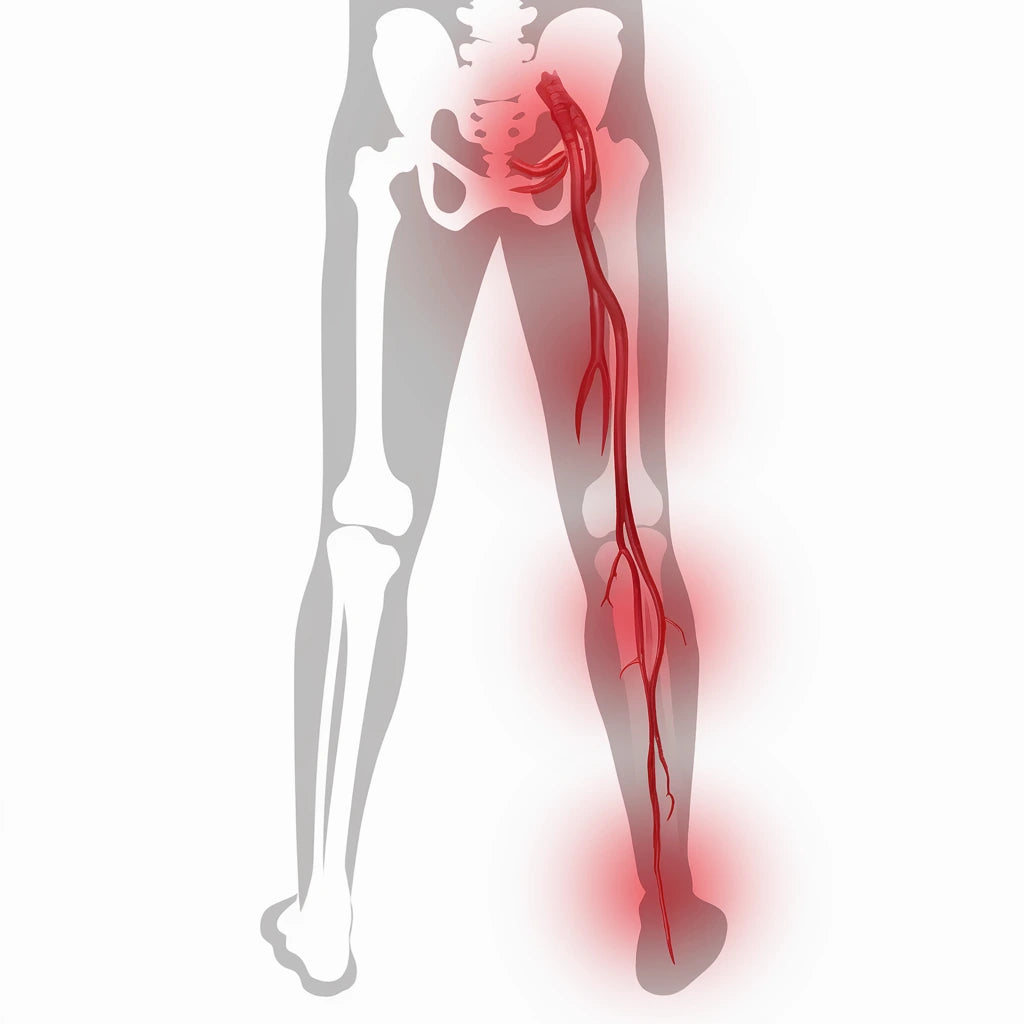

Fötterna bär upp hela vår kroppsvikt – så det är inte konstigt att fotproblem är vanliga. Från hälsporre och artros till brännande känslor och nervpåverkan – vi går igenom orsaker, symtom och möjliga behandlingar. Ta reda på vad dina fotsymtom kan bero på.